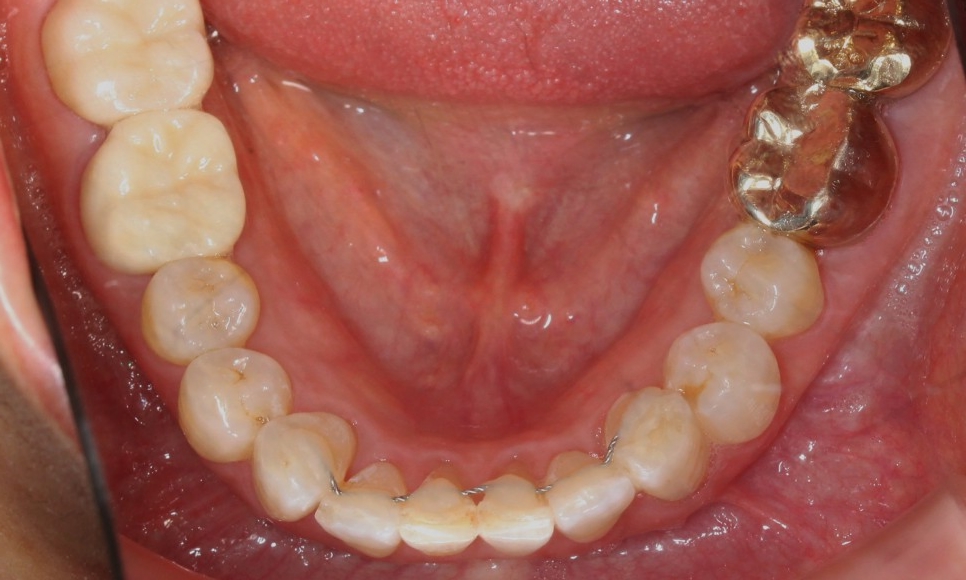

위 사진을 보시면

환자분의 아랫니 상태가

심하게 삐뚤거리는 모습을

확인할 수 있습니다.

치아 사이의 공간이 좁아서

작은앞니의 각도가

심하게 회전된 모습인데요.

전체적인 아랫니의 치열도

심하게 삐뚤거렸던

처음의 모습과는 달리

아랫니 부분교정 (2D교정) 으로

이상적인 치아의 배열인

U자 곡선의 형태로

바뀌었습니다.